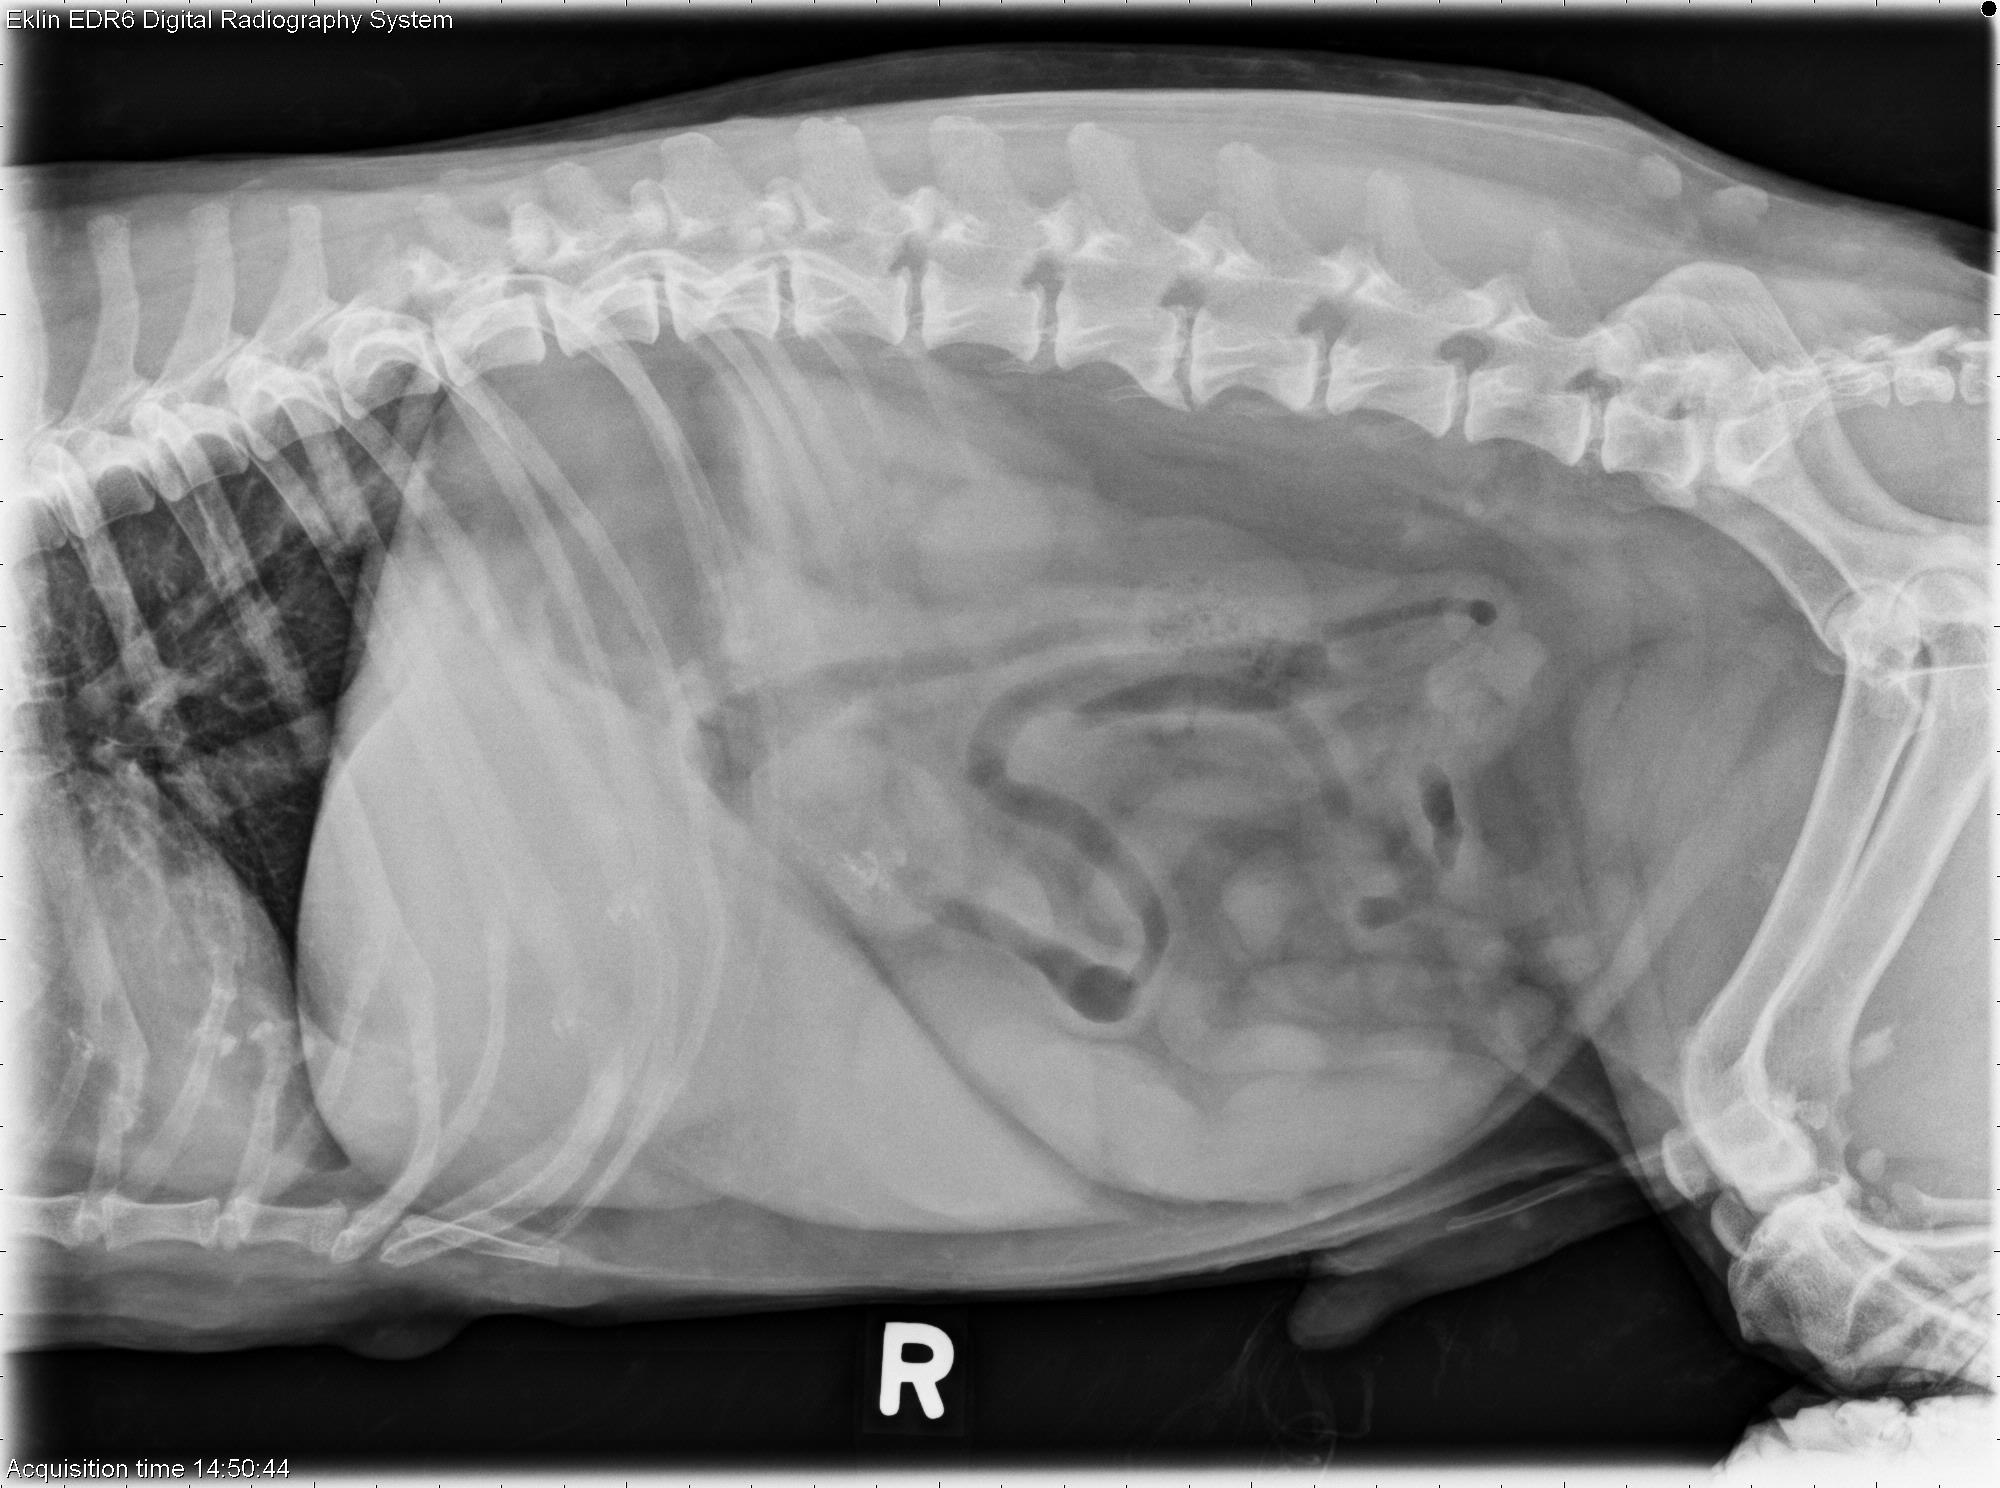

L LAT Abdomen

R LAT Abdomen

VD Abdomen

Abdomen: There is mild abdominal distention and poor detail in the cranioventral abdomen. The liver is enlarged and extends beyond the costal arch. There is a round soft tissue mass superimposed over the caudoventral liver and spleen on the lateral projections. There is widening of the gastroduodenal angle on the ventrodorsal projection, and the duodenum is distended with gas on all projections. The kidneys are normal in size and shape. The bladder is normal. There are small mineral opacities in the region of the urethra caudal to the os penis. The facets of T12-L1 are absent on the left side due to previous laminectomy. In the portion of the thorax included, there is a round soft tissue mass in the left caudal lung lobe.